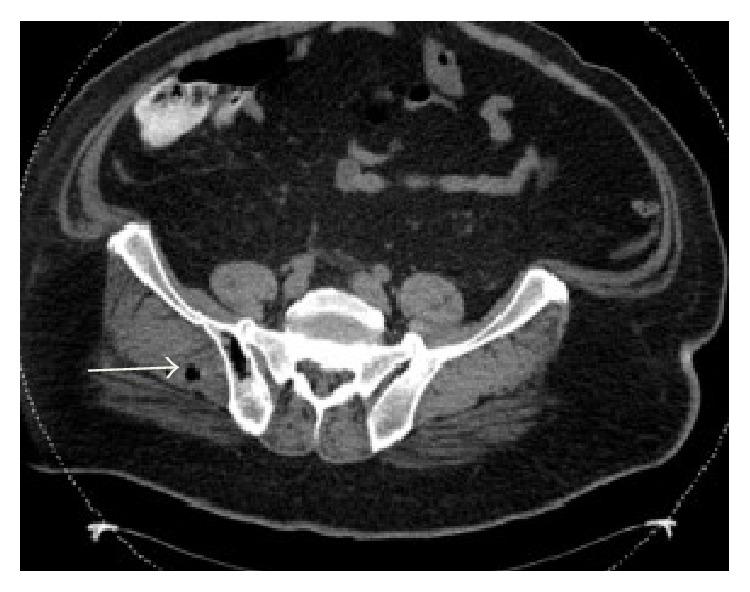

梭菌属细菌可引发一些最为致命的疾病,包括气性坏疽、破伤风和肉毒中毒。败血梭菌是一种罕见的亚群,已知可导致非创伤性肌坏死,且与结肠恶性肿瘤或免疫抑制有关。它是一种革兰氏阳性、厌氧、产芽孢杆菌,存在于胃肠道中,可导致肠道和腹膜腔的直接、自发性感染。肿瘤的无氧糖酵解产生酸性、缺氧环境,有利于梭菌芽孢的萌发。肿瘤引起的黏膜溃疡使芽孢化细菌从肠道转移到血液中,导致暴发性败血症。败血梭菌菌血症的表现可能各异,死亡率超过60%。如果不及时开始诊断和采取适当的治疗措施,大多数死亡发生在最初24小时内。我们报告一例新诊断为结肠癌患者发生腹部肌坏死的病例。本研究的目的是强调对患有潜在结肠恶性肿瘤的患者保持高度怀疑败血梭菌感染的重要性。